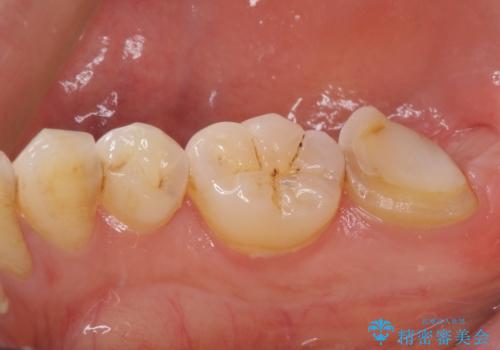

- 根管治療の専門医院で根管治療を行った後、セラミッククラウンによる補綴治療を希望して来院された患者様です。

根管治療後の土台も構築されていたので、仮歯に置き換えた後にフルジルコニアクラウンにて補綴することとしました。